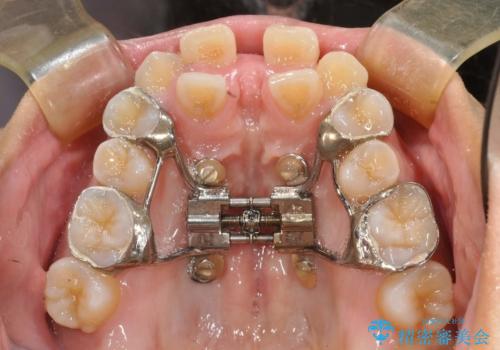

- 上顎の骨格性拡大+両側第1小臼歯抜歯 によりスペースを獲得、フルリンガルによるワイヤー矯正を計画した。